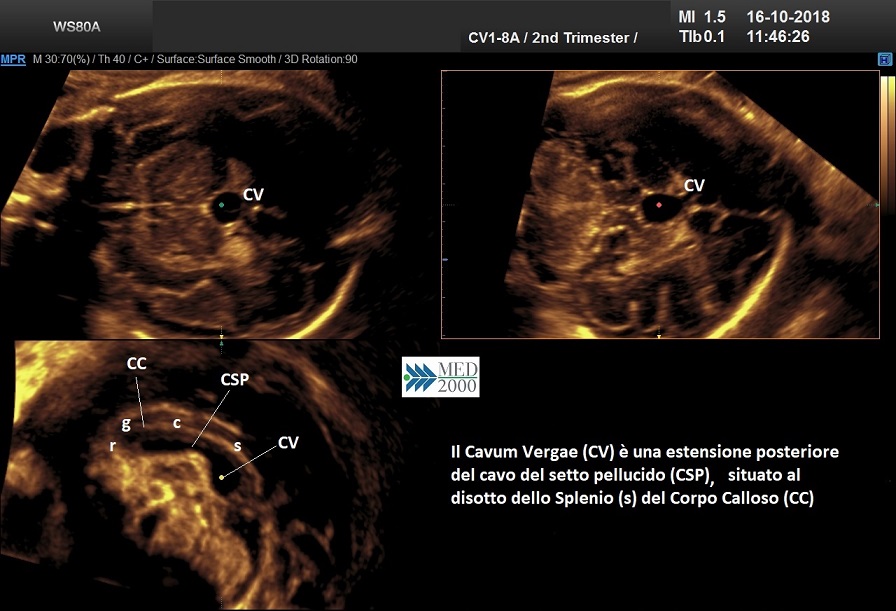

Cavum Vergae

Il cavo del

verga (cavum vergae) è l'estensione posteriore del cavo del setto pellucido nel

periodo fetale; lo si reperta al disotto dello splenio del corpo

calloso e in un 30% dei casi lo si può visualizzare anche nel periodo

neonatale.

Un cavo del verga di piccole dimensioni (< 10 mm.) è considerato fisiologico, mentre un cavo del Verga di diametro trasverso superiore ai 10 mm. (Tao et al. 2013 - Yoona et al. 2017) deve essere meritevole di ulteriori approfondimenti.